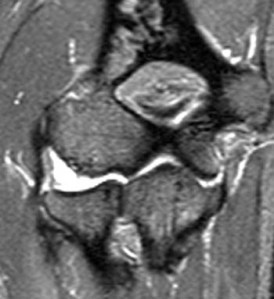

MRI scans can help to show the ligament injury: